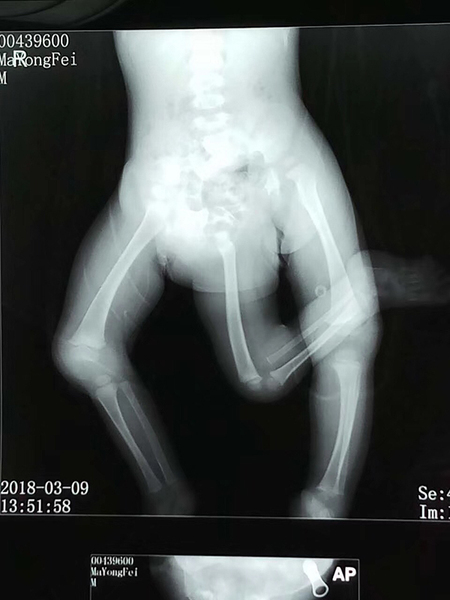

飞飞仅11个月大,体重8公斤,患有先天性疾病,除了多了一条下肢,骨盆还有两个,消化系统、泌尿系统都存在畸形,同时还有先天性心脏病,右睾丸也并未在阴囊内正常发育。

11个多月大的男婴飞飞有三条腿。

影像学检查。严晓慧供图